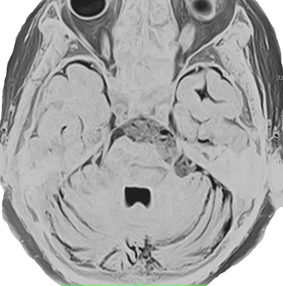

これは1989年に50歳で発症した左三叉神経痛の女性のMRIです。赤いのが類表皮のう胞という良性腫瘍で,黄色く塗ったのが左三叉神経です。腫瘍による圧迫で三叉神経がゆがんでいるのがよく解ります。2010年まで20年間,ほんの少しのカルバマゼピン(テグレトール)の服用で我慢できました。腫瘍は20年の間にゆっくり大きくなって,一時期は左の顔面けいれんもありました。2010年になって眼球運動障害による複視(ものが2重に見える)という症状が出て,年齢も70歳を越えたので開頭手術で腫瘍を摘出しました。術後は目の動きも正常になって三叉神経痛も消失しました。でも,類表皮のう胞の手術はリスクもあって簡単なものではありませんから,手術をすぐに勧める場合と,この患者さんの様にながーく経過を見る場合があります。判断は難しいものです。